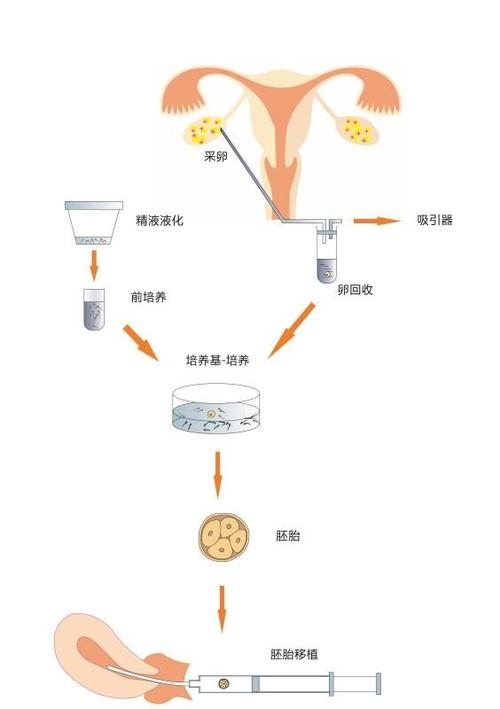

操作技术问题也不容忽视。据《生殖医学进展》2024年的数据显示,约有10%的试管婴儿失败是因为操作技术问题。包括胚胎移植技术、实验室培养环境等。

- 采用ICSI技术,提高受精率

- 引进先进的胚胎培养设备,提高实验室培养环境

- 加强技术培训,提高胚胎移植技术水平